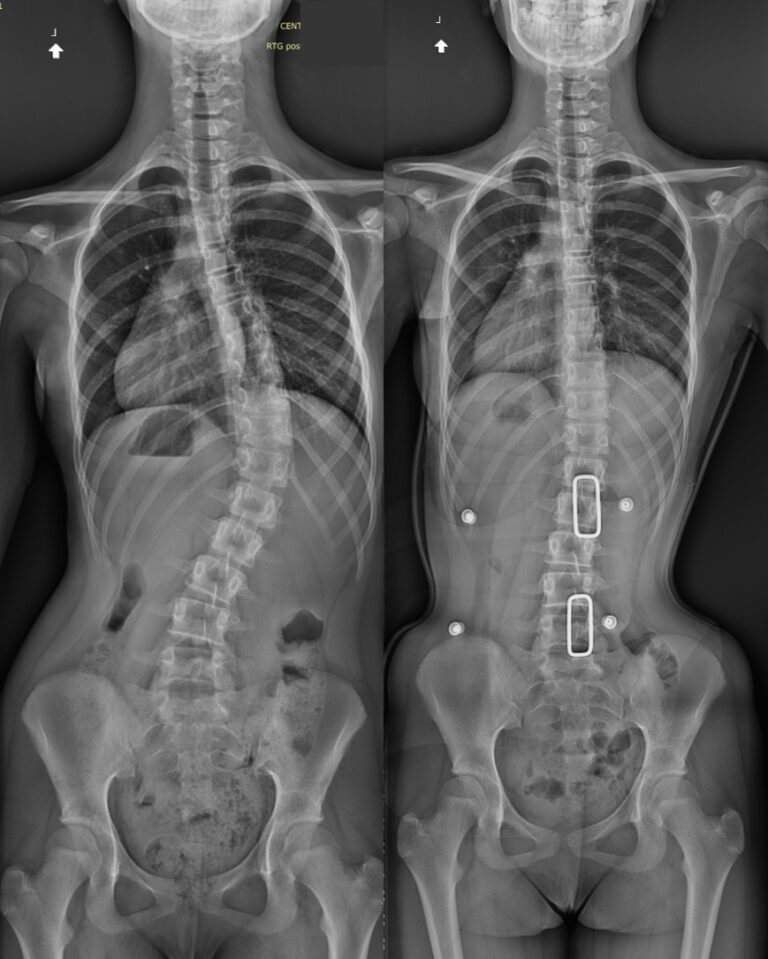

Gorset Cheneau to specjalny asymetryczny gorset ortopedyczny, zaprojektowany do leczenia skoliozy. Wywiera kontrolowany nacisk na wypukłe części kręgosłupa i jednocześnie zapewnia przestrzeń dla korekcji w obszarach wklęsłych.

Jest szczególnie skuteczny u dzieci i nastolatków w okresie wzrostu, gdy ciało jest podatne na korekcję. Jego celem jest zatrzymanie postępu skrzywienia kręgosłupa i poprawa postawy.